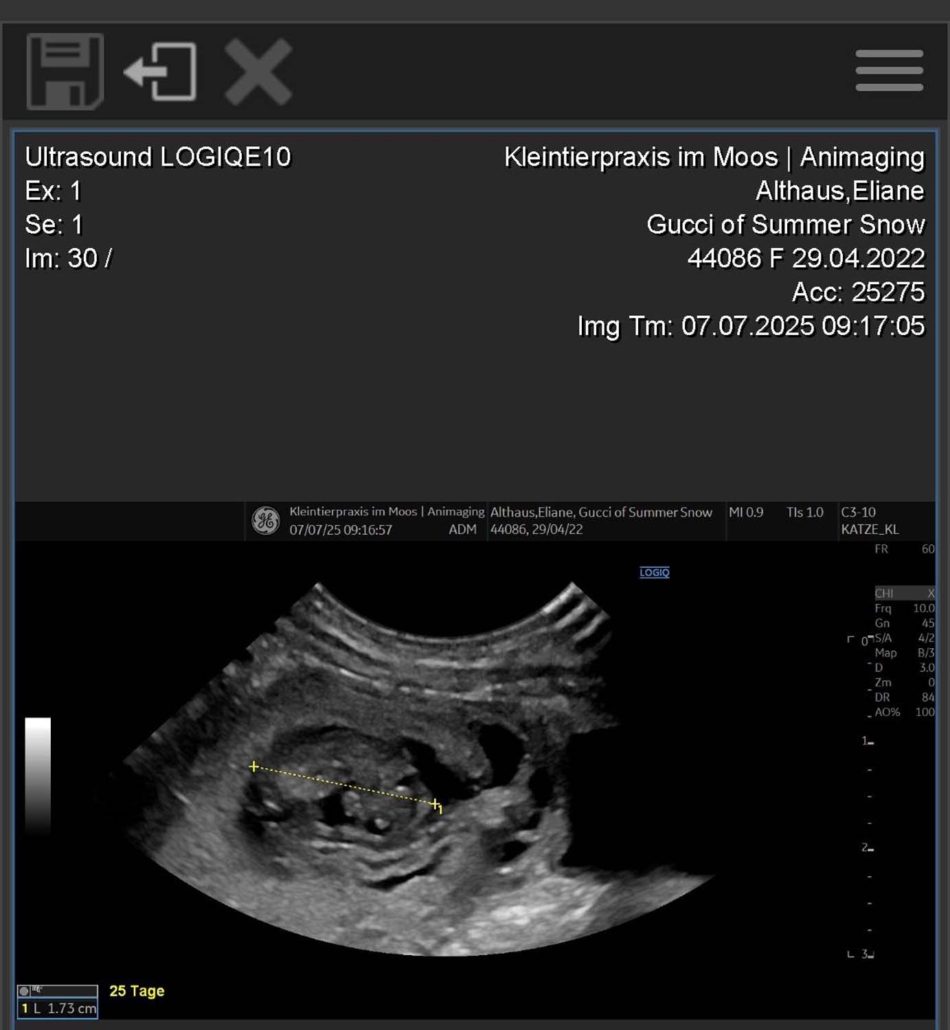

Gucci of Summer Snow | Geboren am 29.04.2022

Gucci ist trächtig – und wir freuen uns riesig auf Mitte August! Auf dem Röntgenbild sind vier kleine Parson Russell Terrier-Welpen zu erkennen! 🐶🐶🐶🐶